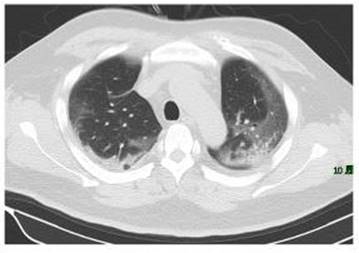

I am trying to perform image segmentation on a CT scan of the lung to detect COVID-19. I have 50 files all in one folder. The folder is already in the matlab path. Please help me... I've been struggling for hours. I attached one picture I am using that is titled